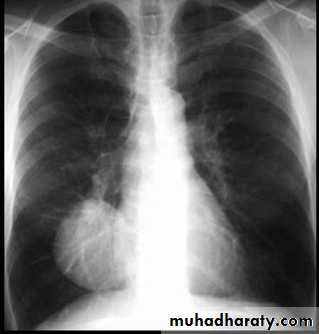

Un complicated Hydatid cyst of th lung , cuased by echenococus granulosis seen as well defined nodule or mass lesion .

Early rupture is sen as a cresnt air sign .ddx aspergillus ball